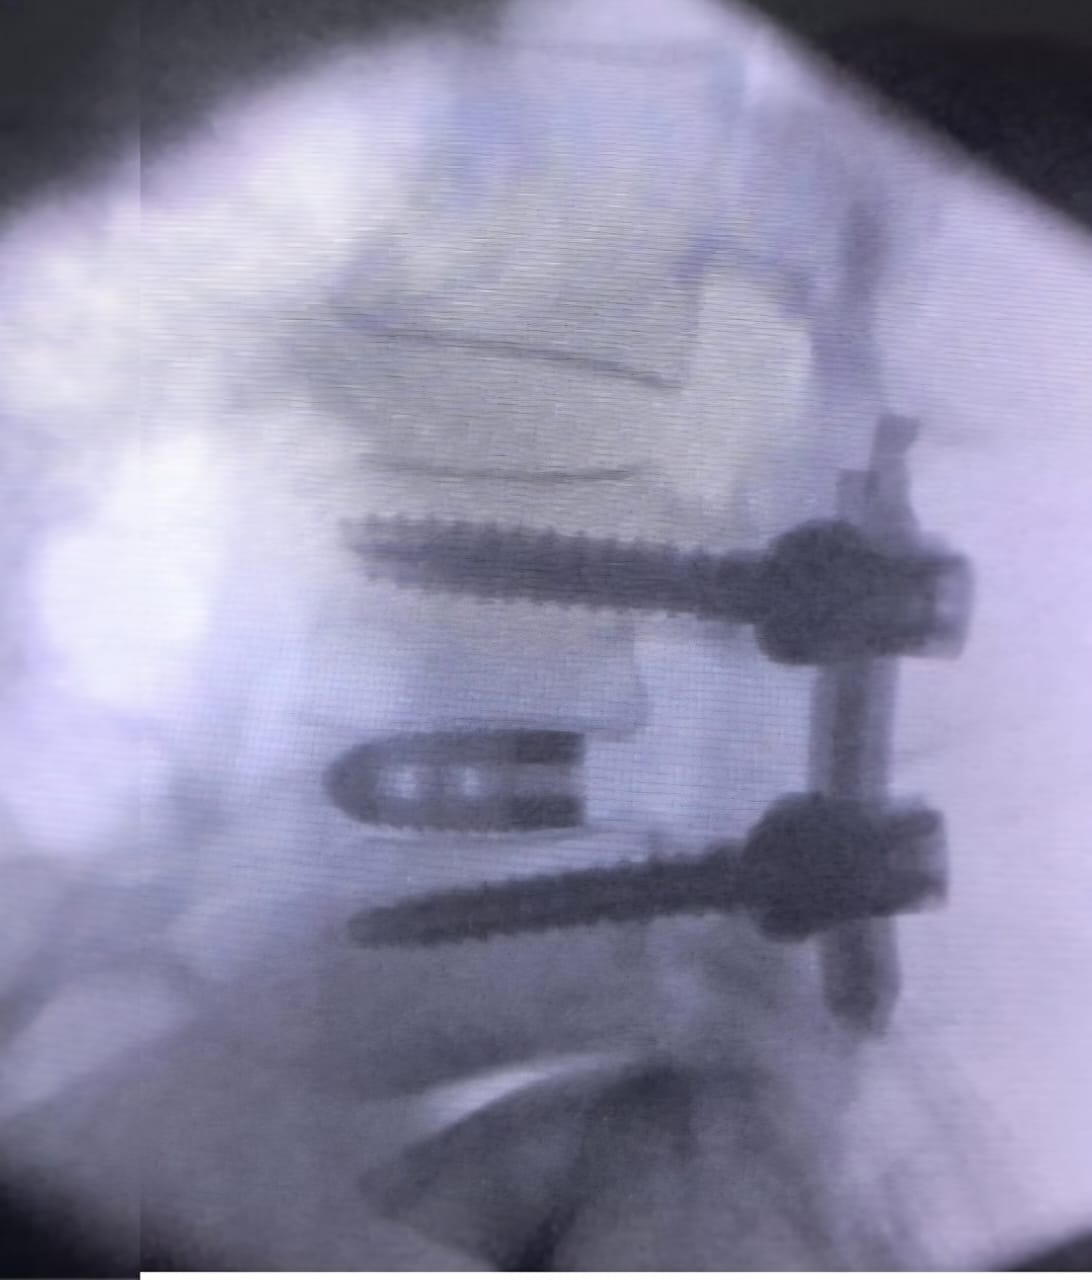

After thorough evaluation, our team opted for a Robotic Endoscopic Transforaminal Lumbar Interbody Fusion (TLIF)*—a next-generation fusion technique that combines:

• Robotic navigation for millimetre-level precision

• Endoscopic visualization for minimal muscle disruption

• Accurate placement of screws and cage for long-term stabili

• Excellent decompression of the nerve roots

• Stable fusion at L4–L5